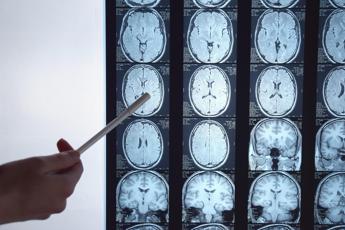

Immunoterapia personalizzata contro il glioblastoma, il cancro al cervello più aggressivo, con una sopravvivenza che dopo 10 anni dalla diagnosi non arriva al 2%. Ad aprire nuove prospettive di cura è il programma Gliomatch finanziato dalla Comunità europea, al quale partecipa l'Irccs Istituto neurologico Besta di Milano. In campo c'è il più grande consorzio di ricerca sui pazienti con glioblastoma multiforme e gliomi di alto grado pediatrici, composto da 8 centri clinici europei. Il Besta descrive il progetto in occasione della Giornata di sensibilizzazione sul glioblastoma. Diverse sperimentazioni cliniche suggeriscono che un sottogruppo di pazienti può trarre beneficio dall'immunoterapia, in particolare quella che utilizza le cellule dendritiche. Da questa osservazione parte il programma di ricerca, che mira a individuare la tipologia di malati per i quali questa strategia può essere utile. Una missione difficile perché per il glioblastoma ancora mancano biomarcatori misurabili, 'spie' della presenza del tumore, della sua evoluzione e della risposta alle cure. "Oggi quasi il 20% dei pazienti affetti da glioblastoma dell'adulto e da glioma pediatrico di alto grado può beneficiare di un trattamento personalizzato in base alle caratteristiche del proprio tumore. Ma in assenza di biomarcatori adeguati, molti ricevono applicazioni di immunoterapia subottimali", spiegano dal Besta. Il team Gliomatch vuole superare questo problema "analizzando, mediante una piattaforma appositamente costruita, i dati clinici molecolari e radiologici di pazienti già trattati in passato con l'immunoterapia". In particolare, illustra una nota, verrà esaminata "la più ampia coorte di pazienti affetti da gliomi di alto grado trattati con immunoterapia (circa 300)". Il consorzio "sfrutterà la potenza dei dati integrando mappe tissutali multistrato a risoluzione spaziale con immagini di risonanza magnetica non invasiva, creando un hub radio multiomico di risonanza magnetica all'avanguardia. In questo modo i medici riusciranno a classificare gli individui in base alle caratteristiche del loro sistema immunitario e a interpretare l'efficacia del trattamento con una precisione senza precedenti". "Siamo orgogliosi di far parte del progetto Gliomatch che io coordino e a cui partecipano anche le dottoresse Serena Pellegatta, Valeria Cuccarini, Bianca Pollo e Catia Traversari", dichiara Marica Eoli, neuroncologa della Neurologia 2, responsabile Ss Neuroncologia sperimentale del Besta. "La condivisione di dati tra diversi centri specialistici è fondamentale per riuscire a riscrivere il futuro dei pazienti affetti da queste forme tumorali molto aggressive", evidenzia. "Il Besta – aggiunge Eoli – è impegnato da tempo nella ricerca di cure personalizzate contro glioblastoma. Il progetto prevede anche, dopo l'analisi degli studi retrospettivi, l'avvio di una sperimentazione clinica che implica la somministrazione della tossina tetanica associata alla vaccinazione con cellule dendritiche sensibilizzate verso il tumore del paziente stesso. E' chiaro che soltanto unendo le forze e potenziando gli sforzi di collaborazione con i nostri partner potremo migliorare le cure e far progredire la ricerca in questo campo". —salutewebinfo@adnkronos.com (Web Info)